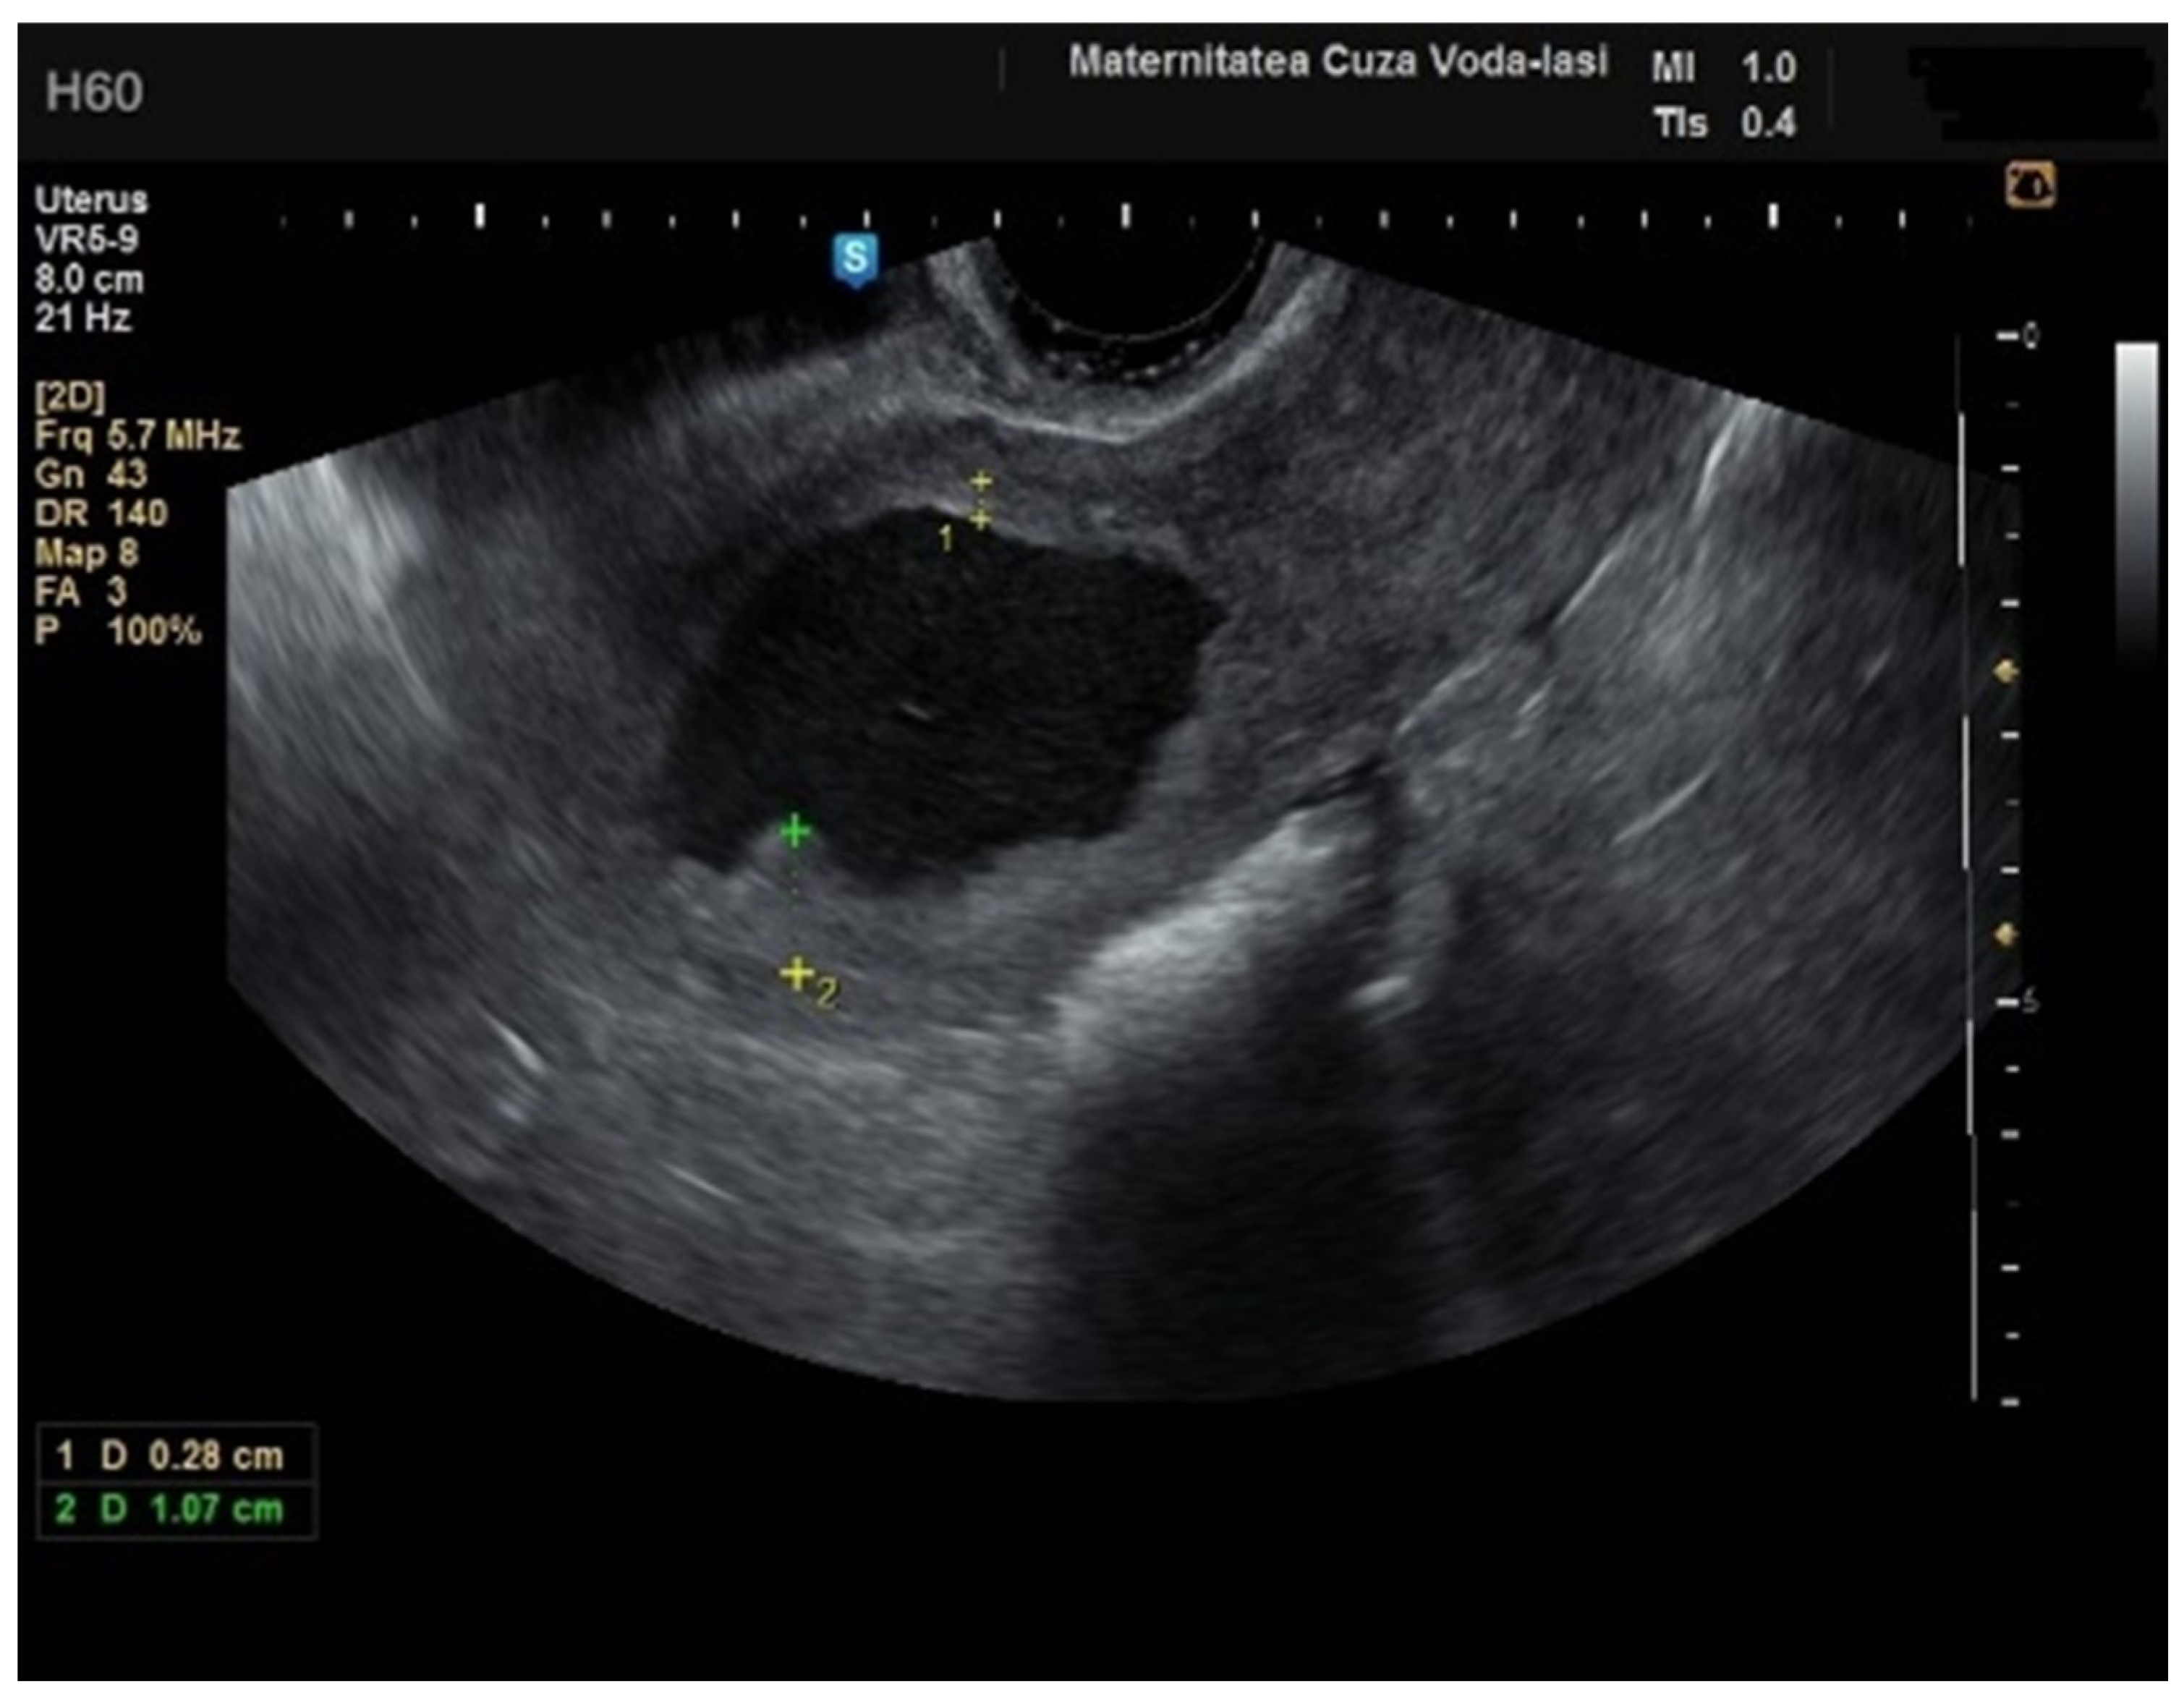

Figure 13. Ultrasound imaging in endometrial cancer: invasion of the posterior myometrium extending less than 50%—without vascularization.

We accurately assessed the depth of myometrial invasion, greater or less than 50%, for all patients with endometrial malignancy (Figure 13 and Figure 14) using a subjective method. Furthermore, the depth of myometrial invasion was also verified preoperatively with magnetic resonance imaging (MRI). In each case of endometrial malignancy, our pathology department appreciated the invasion by conducting a frozen section during surgery, as well as through the final paraffin-based histopathological exam.